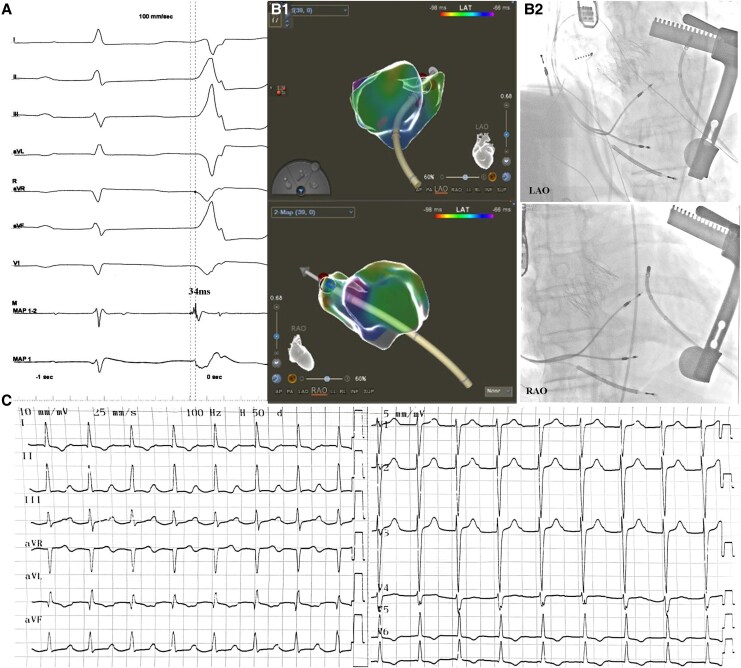

Case summary: We present a 67-year-old male with dilated cardiomyopathy, severe aortic regurgitation, and unifocal left ventricle-originated PVCs (37.8% burden) refractory to guideline-directed medical therapy and cardiac devices. Due to high surgical risk, a combined transapical transcatheter aortic valve implantation and PVC ablation was performed. Postoperatively, PVCs were eliminated, left ventricular ejection fraction improved from 35% to 55%, and cardiac dimensions normalized significantly.

Discussion: This case highlights the feasibility of a single apical approach for addressing both valvular and arrhythmic pathologies in high-risk patients, offering a novel strategy to mitigate heart failure progression.